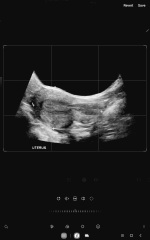

Thanks for your input, I would have been approx 11 weeks at the time of the scan image posted I did have another mid November. Still no talk just felt dismissed, no report just on my uterus measurements and Ovaries which was fine. I feel so challenged and then another person told me they could see a foot then another a femur. I feel like a pest but told to insist it be investigated further as bub might not be showing within the perimeters due to tilted uterus, no movement to date but would be approx 18 weeks and counting. My GP trips are getting to me mentally and I practically smile to myself knowing how predictable her text or narrative is going to be. This is Mid November someone told me they see a foot????? A femur as bones are usually bright but I fail to see this. Am I missing something. My health is otherwise great with pathology etc. Can't have TV as have had before and I leave spotting light pink for a day and half 2 days after the TV ultrasound therefore my GP agrees with me on one thing not to do TV anymore just abdo with full bladder. Kidneys, liver, spleen ovaries everything else is fine. I hope this child if there is one isn't squashed up or multiples distorting the pic. I would feel terrible but not at fault as no one is picking this up. I will attach the Nov scan for any feedback of feet or femur. Can you tell me the points they have marked out as no one explained again. TiA